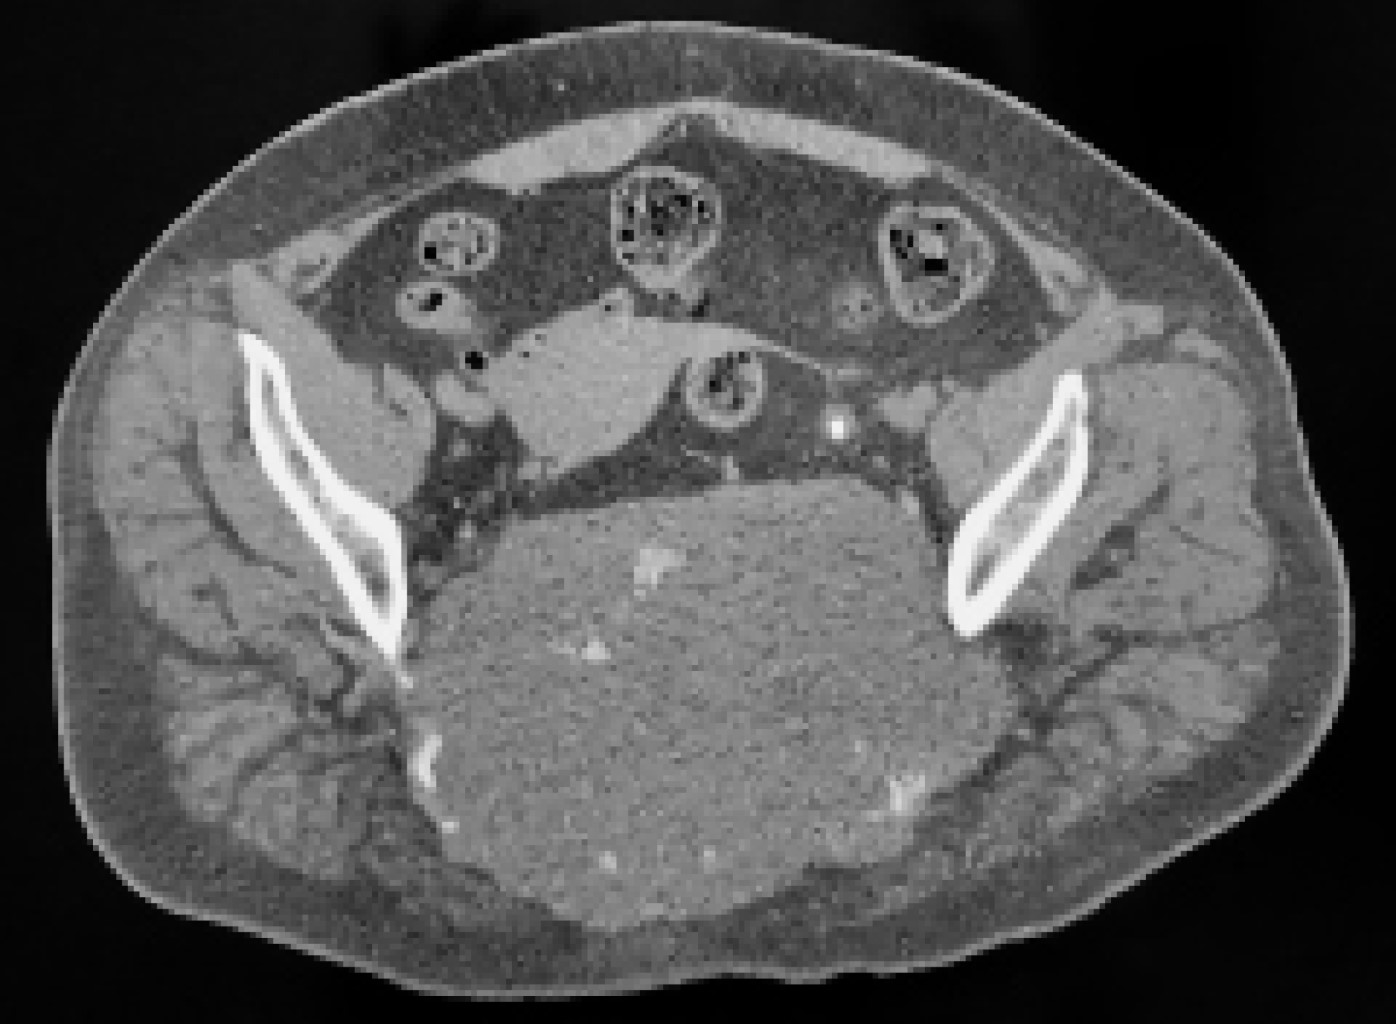

Figura 1

Figura 2

Figura 3

Figura 4

Figura 5

Figura 6